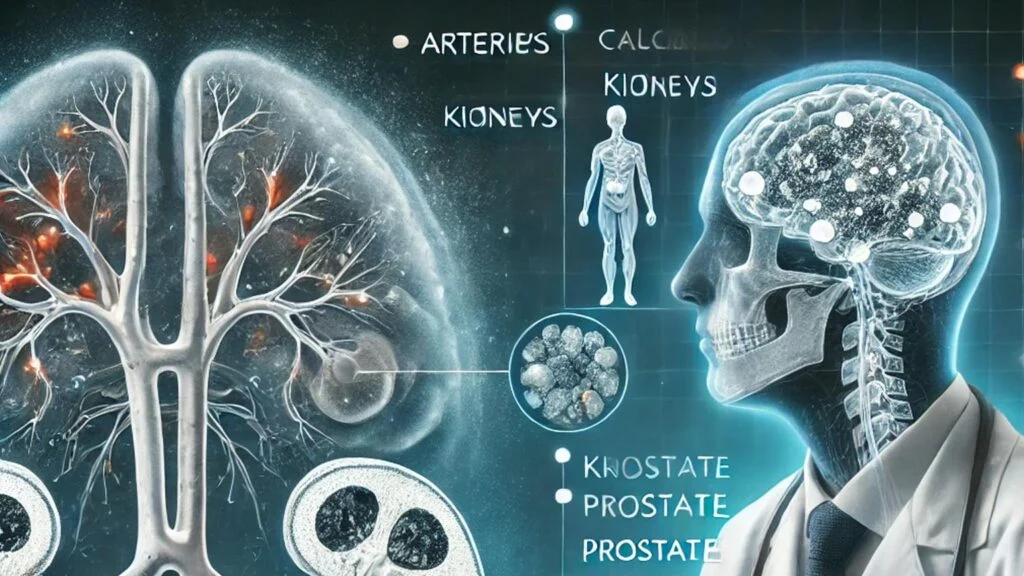

آیا کلسیفیکاسیون خطرناک است؟

آیا کلسیفیکاسیون خطرناک است؟ کلسیفیکاسیون یکی از فرایندهای طبیعی بدن است که در آن کلسیم در بافتهای نرم بدن رسوب میکند. این پدیده ممکن است در قسمتهای مختلف بدن مانند شریانها، کلیهها،…

آیا کلسیفیکاسیون خطرناک است؟

آیا کلسیفیکاسیون خطرناک است؟ کلسیفیکاسیون یکی از فرایندهای طبیعی بدن است که در آن کلسیم در بافتهای نرم بدن رسوب میکند. این پدیده ممکن است در قسمتهای مختلف بدن مانند شریانها، کلیهها، مفاصل، پروستات و مغز رخ دهد. بسیاری از افراد هنگام مشاهده…